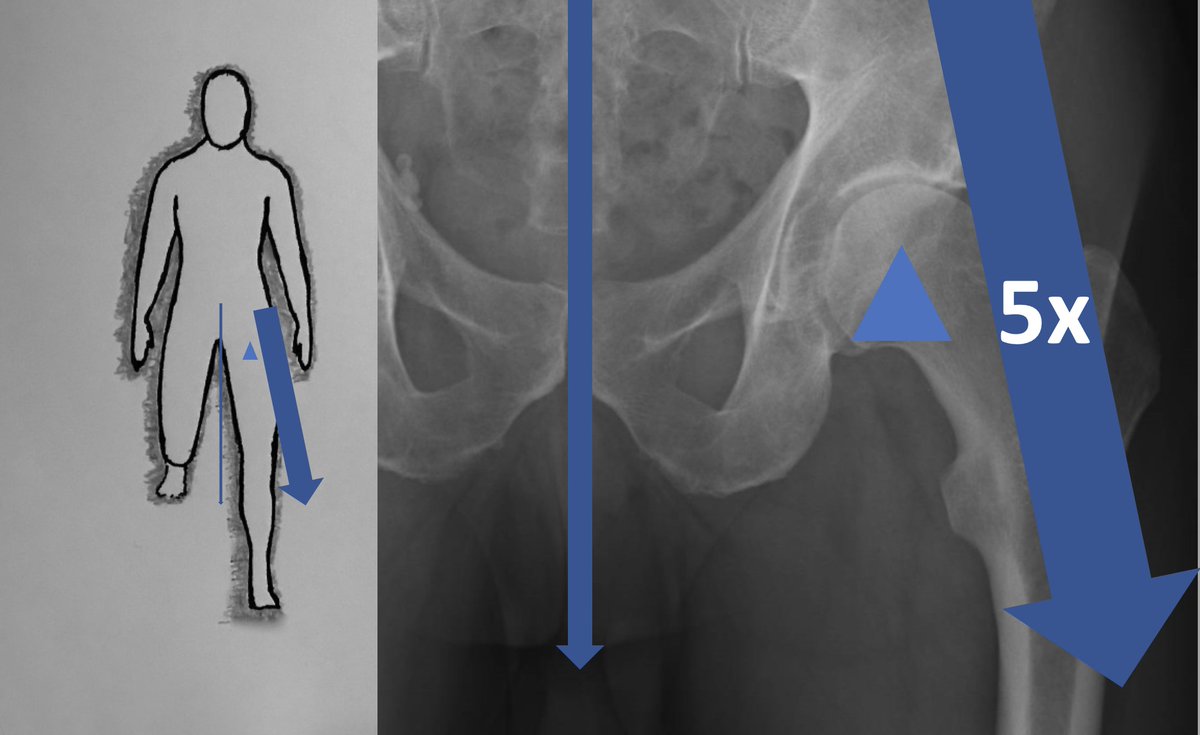

These are expensive too and a lot of hard work goes into getting pt on table. Thank you to YGC theatres & staff for the effort, @BetsiCadwaladr for support, fantastic MDT Wrightington, North Wales MDT, surgical experience @CavendishHip, my colleagues & Mr Kapur for dual operating